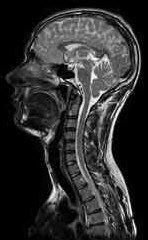

Die MRT ist unbestritten dasjenige Verfahren, mit dem man heute am besten Bilder des Nervensystems und seiner Erkrankungen anfertigen kann. Für einige Fragestellungen ist zwar die Computertomographie ausreichend, die MRT wird aber zunehmend eingesetzt.

Das gilt nicht nur für das Gehirn, sondern auch für den Rückenmarkskanal und das darin verlaufende Rückenmark sowie die Nervenwurzeln.